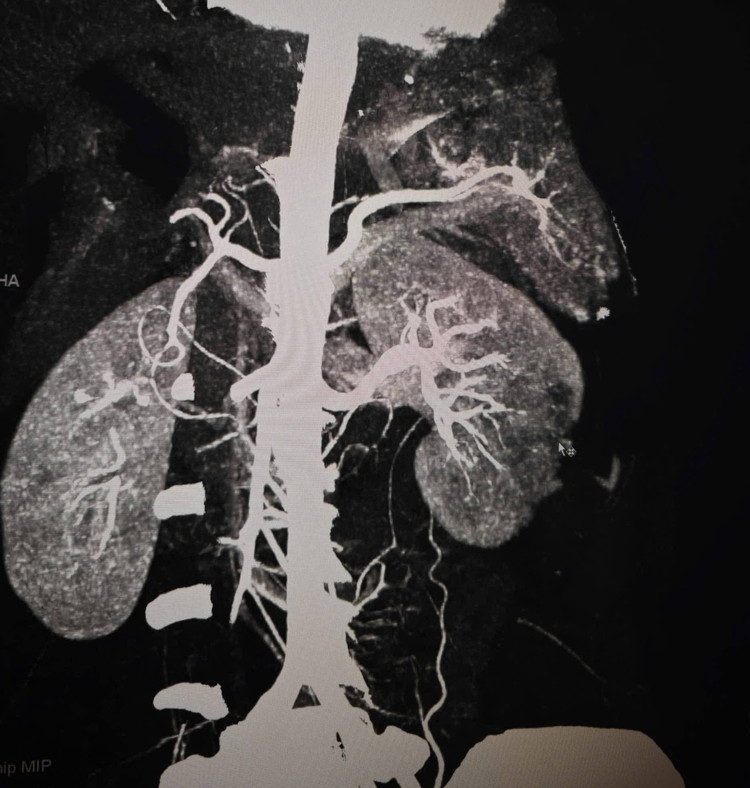

Hình ảnh thận và lách vỡ trên phim chụp - Ảnh BVCC

Sau hội chẩn nhanh giữa Cấp cứu – Ngoại tổng hợp – CĐHA, các bác sĩ nhận định tổn thương mạch máu khu trú, phù hợp ưu tiên can thiệp nội mạch cầm máu nhằm tránh một cuộc mổ lớn nhiều rủi ro.

Tại phòng can thiệp mạch, dưới hệ thống chụp mạch số hóa xóa nền (DSA), các bác sĩ Khoa Chẩn đoán hình ảnh xác định điểm chảy máu và giả phình ở cả lách và thận, sau đó tiến hành nút tắc các nhánh mạch tổn thương. Toàn bộ thủ thuật diễn ra trong khoảng 45–60 phút.